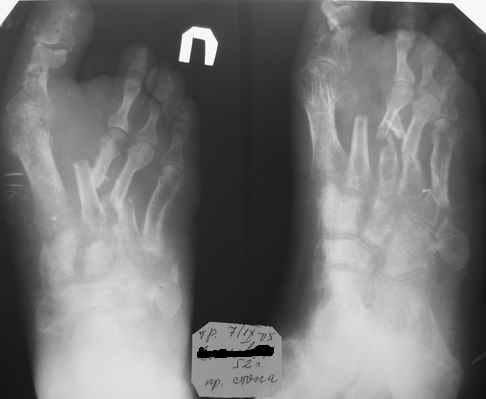

Alexey Mozgunov 11 Сентябрь 2005, 14:35

АМ> Стабилизация в АВФ на третий день.

Что самое интересное (как следует из снимков) стабилизация в аппарате

не привела к улучшению рентгенологичской картины...

Зачем нало было так стабилизировать?